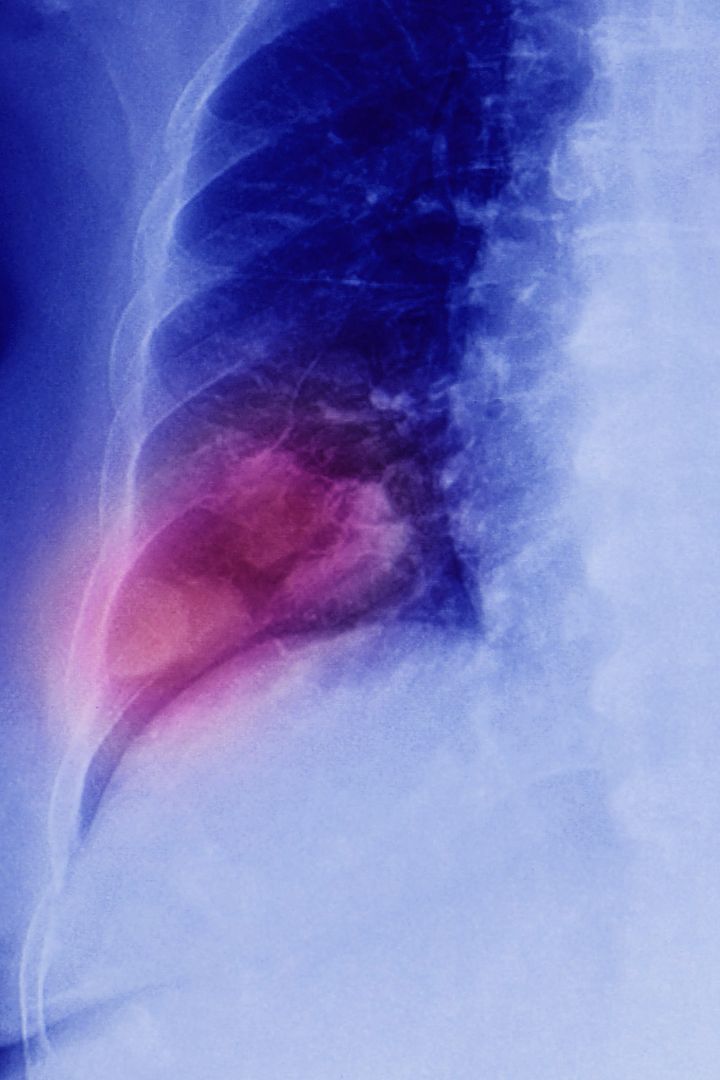

What is mesothelioma?

Mesothelial cells cover most internal organs. Mesothelioma is a cancer affecting these cells.

There are two types of mesothelioma:

• pleural mesothelioma, which starts in the membranes that cover the lungs and accounts for 90% of cases

• peritoneal mesothelioma, which develops in the lining of the abdomen and accounts for 10% of cases.

The only known risk factor for mesothelioma is exposure to asbestos. In rare cases, mesothelioma can also occur around the heart or reproductive organs.